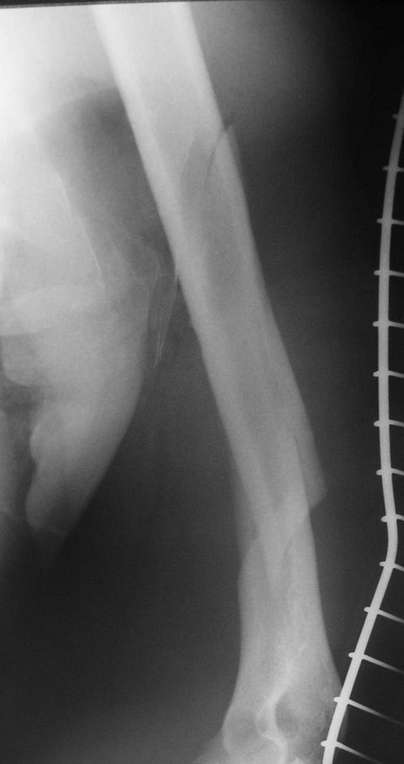

Позвольте привести пример из собственной московской практики в поддержку тактики, приведенной в данном примере. Пациент переведен из одной из московских клиник на 3 сутки после сквозного огнестрельного ранения плеча(пистолет)с ушитыми узловыми швами и дренированными резиновым выпускником ранами на внутренней поверхности плеча с умеренным серозногнойным отделяемым и похожей раной на задненаружной поверхности грудной клетки (пуля прошла через плечо и остановилась в мышцах спины). Также имелись реактивный локтевой бурсит и нейропатия локтевого нерва. При поступлении были сняты швы, начата антибиотикотерапия. Через сутки после травмы пациент прооперирован: выполнена повторная хирургическая обработка ран плеча и грудной клетки. Через отдельные доступы на наружной поверхности плеча произведен минимально инвазивный остеосинтез плечевой кости блокируемой метадиафизарной пластиной. Пациент выписан на 4 сутки после операции. Дальнейшее течение гладкое, все раны зажили первичным натяжением. Еще раз пациент был госпитализирован через 4 месяца после операции с переломом этого же плеча на границе средней и дистальной третей: коллеги по криминальному ремеслу применили к нему слишком жесткие меры убеждения. Выполнен остеосинтез путем замены и добавления винтов в дистальной части пластины. Госпитализация 2 суток. К сожалению, последние снимки не сохранились.